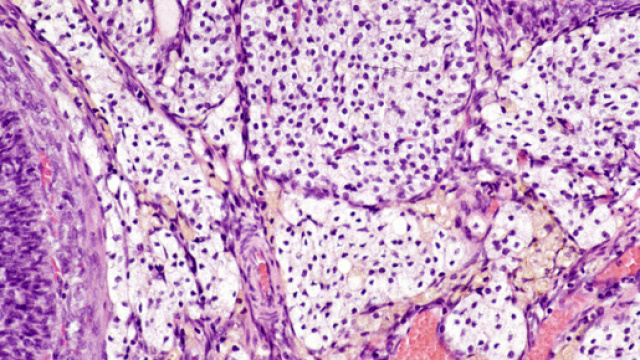

E' stato possibile scoprire l'interstizio grazie ad una tecnica all'avanguardia: l'endomicroscopia confocale laser, che permette di osservare al microscopio i tessuti in vivo, ovvero in diretta nel corpo, senza bisogno di prelevarne una porzione e posizionarla sui vetrini.

I tessuti esaminati appartengono ad un campione di pazienti oncologici in attesa di resezione di dotto biliare e pancreasectomia. In questo modo è stato possibile vedere la vera struttura dell'interstizio, ritrovata poi in tutte le altre aree del corpo che ricevono sollecitazioni e pressione. Dal momento che esso è diffuso dappertutto è da considerare un vero e proprio organo, e la sua presenza dà adito a nuove ricerche mediche, che si baseranno sul campionamento del fluido interstiziale come strumento diagnostico. Il fluido infatti è in perpetuo movimento e il flusso spiega come i tumori che insorgono in queste zone o le invadono siano diffusi in maniera più rapida; dal drenaggio del fluido la linfa che attraverso la circolazione linfatica rende possibile all'azione delle cellule immunitarie.